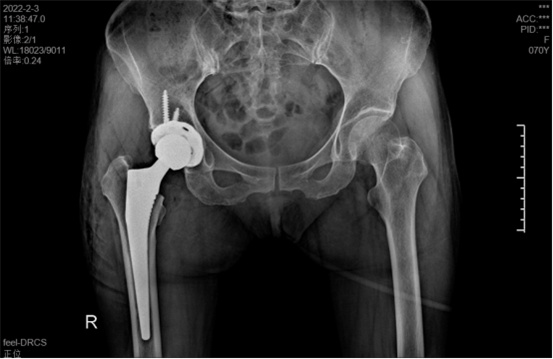

據(jù)羅軍主任介紹,他們首先將鄭阿姨的術(shù)前CT數(shù)據(jù)導(dǎo)入到系統(tǒng)中,通過自動(dòng)識(shí)別骨盆和股骨建立了計(jì)算機(jī)數(shù)字三維模型。AI HIP顯示患者適合使用合適的髖臼杯、股骨柄、標(biāo)準(zhǔn)陶瓷球頭、陶瓷內(nèi)襯,并精準(zhǔn)定位了截骨線,有效幫助醫(yī)生在手術(shù)中做到精確截骨。

在完善相關(guān)檢查充分評(píng)估患者身體情況及手術(shù)風(fēng)險(xiǎn)后,羅軍主任改變傳統(tǒng)手術(shù)方式,在易觀俊主治醫(yī)師、柴重喜醫(yī)師等助手的配合下,為鄭阿姨實(shí)施了人工智能規(guī)劃輔助DAA入路全髖關(guān)節(jié)置換術(shù)。

術(shù)中假體植入和術(shù)前規(guī)劃完全一致

術(shù)中,醫(yī)生在患者髂前上棘外側(cè)切開約8cm長的切口,小心翼翼地利用闊筋膜張肌與縫匠肌之間的間隙露出髖關(guān)節(jié)。經(jīng)過一番精細(xì)、高難度的操作,成功植入人工髖關(guān)節(jié)組件,以取代受損的股骨頭和髖臼。由于手術(shù)切口小,肌肉組織未受損,鄭阿姨恢復(fù)很快,術(shù)后第1天就能下床活動(dòng)。